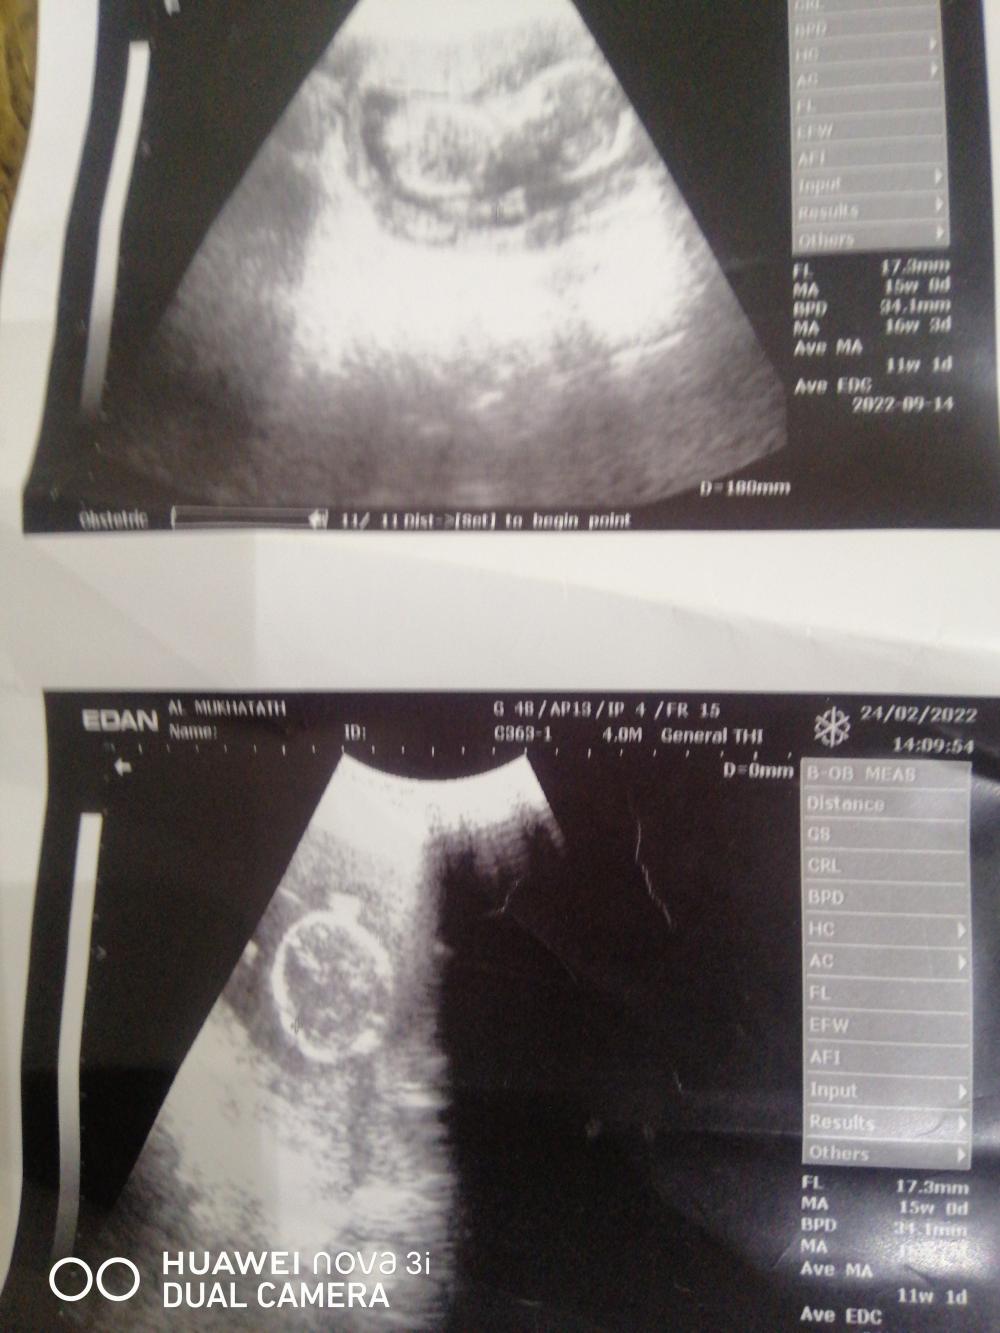

السلام عليكم انا داخله بالرابع لي اسبوعين اليوم سويت سونار تقول مقفل رجوله اللي تعرف بالسونار بنزل صورته